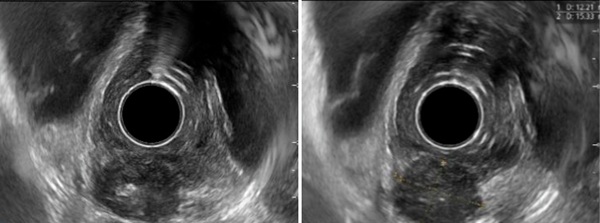

超声内镜下,答案越来越清晰

随后,我继续进行了超声内镜检查。

在病变部位扫查时,可以看到:

· 食管壁外有一个类圆形低回声病灶

· 低回声中央可见高回声区

· 病灶已经累及并侵透食管壁

这样的表现提示,病变很可能来源于食管旁淋巴结,并进一步侵犯食管壁。

结合胃镜表现,我更加确信自己的判断:

食管壁外低回声病灶,考虑淋巴结侵及食管壁,食管结核可能性大。

超声内镜表现